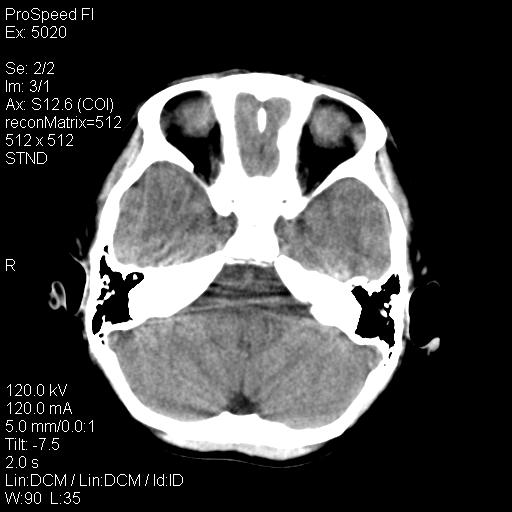

标题: PED1637:M 6Y 顶部无痛性包块两月。 [打印本页]

标题: PED1637:M 6Y 顶部无痛性包块两月。

2、颅骨局部缺失,边缘光滑、整齐

颅骨的病损表现为内外颅骨板层不规则的锋利的破坏,形成“斜边缘”,有一定的特点

颅骨为好发部位,生长缓慢,常位于顶骨、枕骨及颞骨,表现为颅骨缺损,呈圆形或椭圆形,边界清,无硬化

事发冠状缝与矢状缝交界区,密度较低,考虑表皮样囊肿可能性大,其次不除外嗜酸性肉芽肿